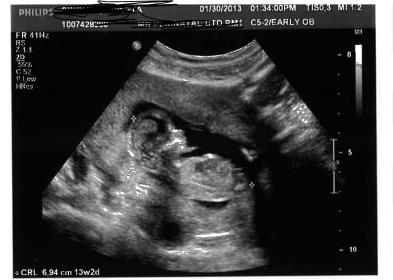

These were taken at 13w3D

Update ** I am adding one more pic if that helps

Attachment 8855Attachment 8856

Thanks in advance.

What is the circled part?

Thank you ladies..... I am soooo hoping for a boy. But I have a gut feeling that it is a girl. I will be happy either way. I am 15 weeks now.... will schedule an appointment for 20W ultrasound pretty soon. I can totally go to an elective place ( only 99$) but I am just so nervous about finding out gender. I am worried about gender disappointment.

thanks Inky. So what is that white thing in the bottom? I thought that was nub.